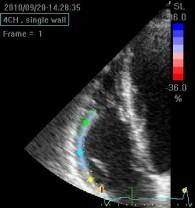

Echokardiografie: LEVÁ KOMORA bez dilatace a hypertrofie, s normální systolickou funkcí a regionální kinetikou kromě D shape, EF LK 55-60%. Diastolická funkce: porucha relaxace LK. PRAVÁ KOMORA FAC PK 18%, TAPSE 13 mm, Vt 9 cm/s, dilatace a hypertrofie PK, těžká prekapilární PH, odhadovaný PASP 90 mmHg, MPAP 55 mmHg, malý perikardiální výpotek

Echokardiografie: LEVÁ KOMORA bez dilatace a hypertrofie, s normální systolickou funkcí a regionální kinetikou kromě D shape, EF LK 55-60%. Diastolická funkce: porucha relaxace LK. PRAVÁ KOMORA FAC PK 19%, TAPSE 17 mm, Vt 9 cm/s, dilatace a hypertrofie PK, těžká prekapilární PH, odhadovaný PASP 130

mmHg, perikardiální výpotek